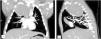

La radiografía de tórax mostraba una opacidad completa en el lóbulo superior derecho (fig. 1), mientras que las ecografías pulmonares seriadas eran normales (fig. 2A). La ecografía torácica realizada desde el plano supraclavicular mostraba una consolidación bien definida sugestiva de masa torácica (fig. 2B y vídeo 1) que se evidencia en la TAC (fig. 3). La biopsia confirma el diagnóstico de neuroblastoma congénito.

TAC torácica con administración con contraste intravenoso. Masa en mediastino posterior de 4,6×4,3×6,3cm con realce heterogéneo y pequeñas calcificaciones en su interior que ejerce efecto masa desplazando estructuras adyacentes y comprimiendo el lóbulo superior derecho. A)Corte coronal. B)Corte sagital.

El 5% de los neuroblastomas se manifiestan en periodo neonatal1, estando localizados hasta el 15% en el tórax2, pudiendo causar dificultad respiratoria y estridor. La sospecha inicial de bronquiolitis complicada con neumonía o atelectasia, basada en los hallazgos radiológicos, fue reconsiderada tras la normalidad de la ecografía, motivando la evaluación de otras regiones. La discrepancia entre las pruebas de imagen debe hacernos sospechar otros diagnósticos3. Aunque las masas torácicas son raras en neonatos, una consolidación radiológica con patrón ecográfico pulmonar normal puede sugerir dicho diagnóstico.